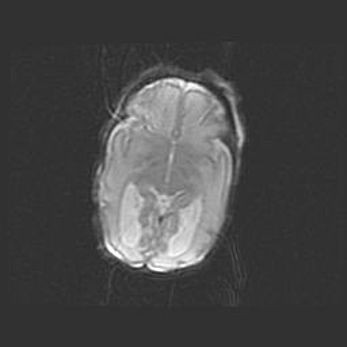

Церебральная ишемия II.

Возраст: 5 дней

Вес: 3400 г

Пол: женский

Окружность головы: 35 см

Срок гестации: 39 недель

Церебральная ишемия – это заболевание, характеризующееся недостаточностью (гипоксией) либо полным прекращением (аноксией) снабжения мозга кислородом по причине закупорки одного или нескольких сосудов. Это приводит к  что метаболическим расстройствам различной степени тяжести в тканях головного мозга, развитию коагуляционных некрозов и гибели нейронов.